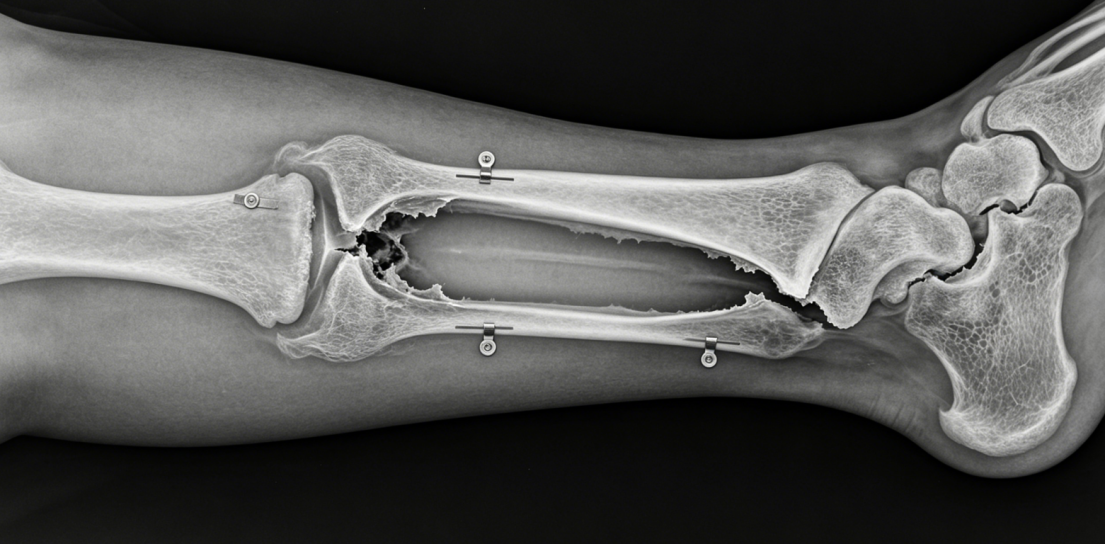

Clinical Scenario – Post-Traumatic Tibial Bone Defect

A 40-year-old sustains a Gustilo IIIB open tibial fracture with 5 cm of bone loss. After debridement and soft tissue coverage, a ring fixator is applied. A proximal corticotomy is performed. Distraction begins at 1 mm/day. The transport disk moves distally, and new bone forms in the proximal gap. After 50 days, the transport disk docks with the distal fragment. Compression is applied at the docking site. The total frame time is 8 months. Radiographs show healed regenerate and docking site. The patient returns to walking without limb length discrepancy.